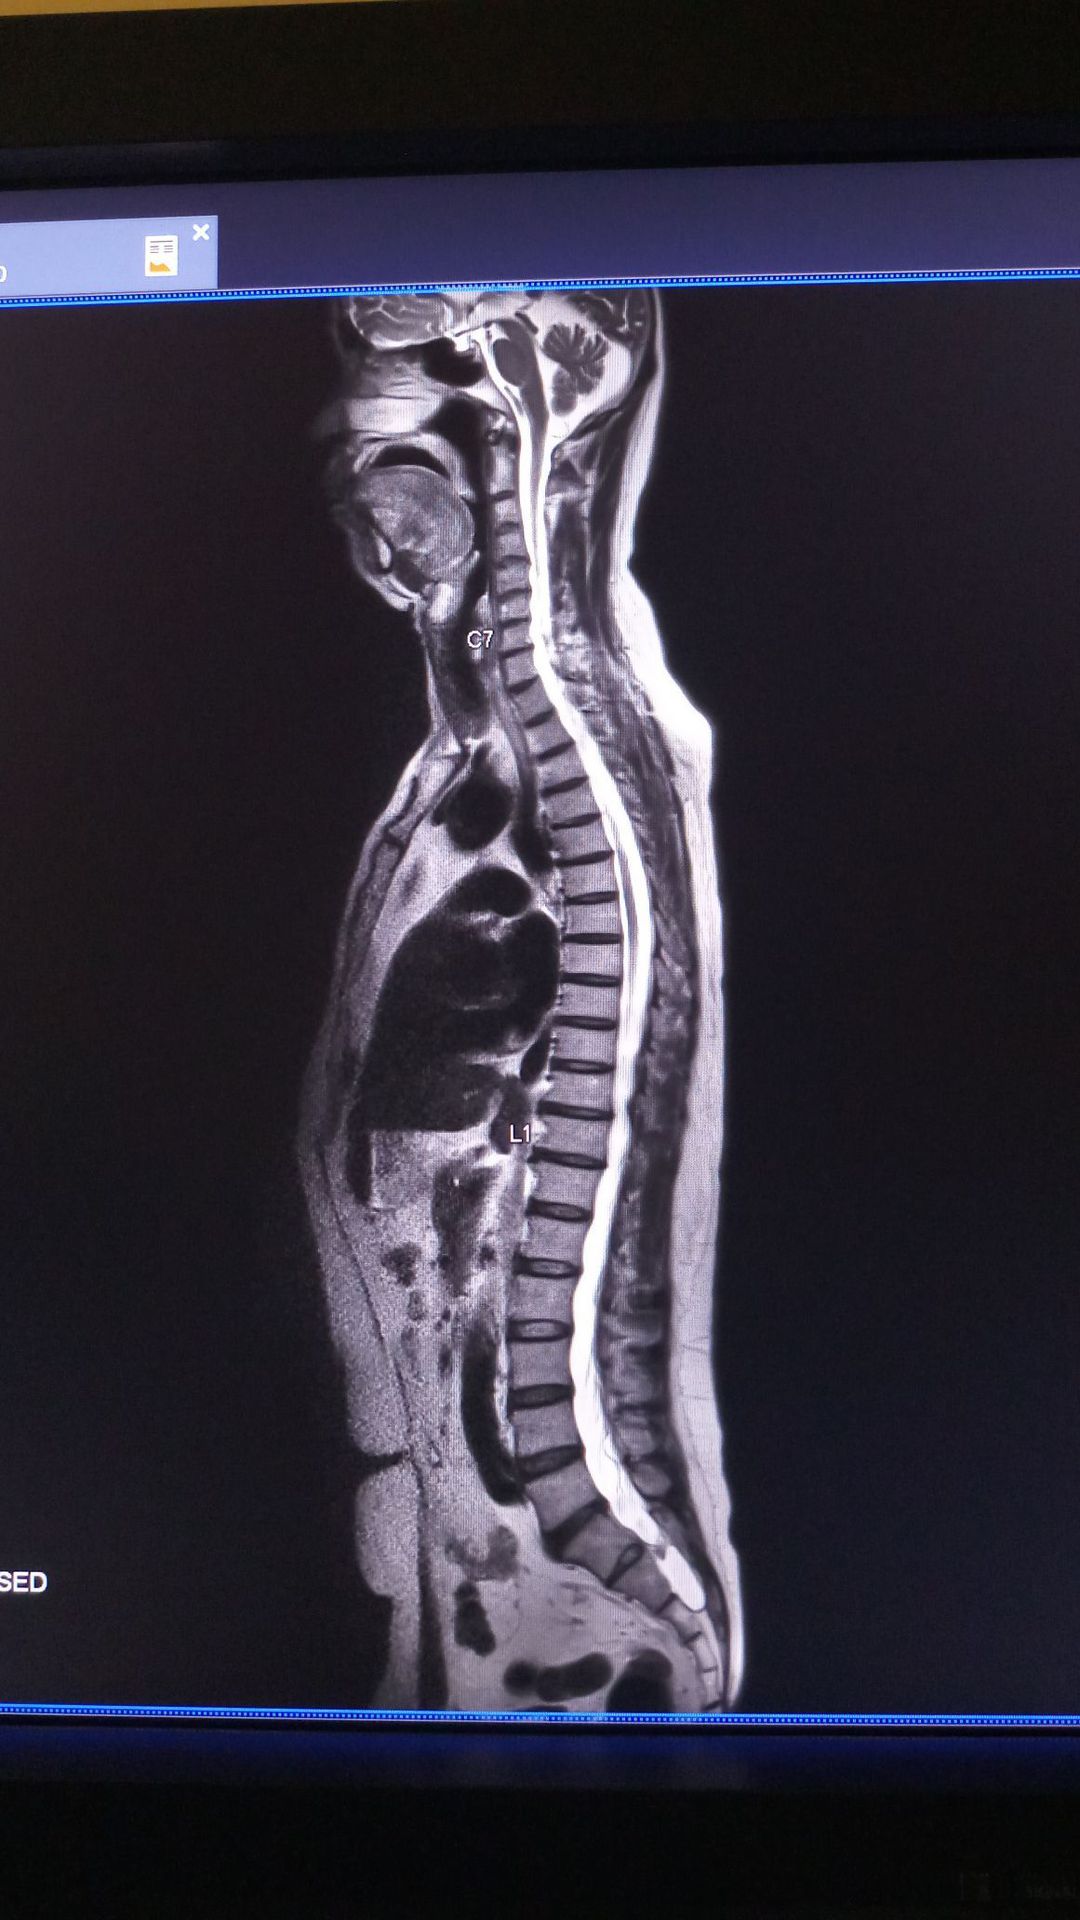

Lumbarization...

Comminuted Lumbar Vertebral Fracture

Presentation of lumbar Radiculopathy

Vertebral Levels